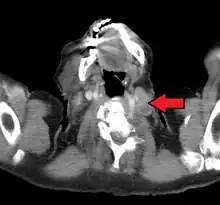

El nódulo de Virchow (también llamado nódulo de Troisier o nódulo de Virchow-Troisier )[1] es un ganglio linfático situado en la fosa supraclavicular izquierda (el área por encima de la clavícula izquierda). Recibe el drenaje de vasos linfáticos en la cavidad abdominal. El descubrimiento de un nódulo agrandado y endurecido ha sido largamente considerado como un fuerte indicativo de la presencia de cáncer en el abdomen, específicamente cáncer gástrico, que se ha expandido a través de los vasos linfáticos. Por esta misma razón a veces se lo llama nódulo señal o nódulo centinela. Pese a esto, el concepto no está directamente relacionado con el procedimiento del nódulo centinela que a veces se utiliza en cirugía oncológica, y tampoco tiene relación con la "glándula centinela" del epiplón mayor.

Los procesos malignos de los órganos internos pueden alcanzar un estado avanzado antes de dar síntomas. El cáncer gástrico, por ejemplo, puede permanecer asintomático mientras ocurre metástasis. Uno de los primeros puntos visibles donde estos tumores se propagan es el ganglio linfático supraclavicular izquierdo.

El ganglio supraclavicular izquierdo es el nódulo de Virchow clásico porque es en el lado izquierdo del cuello donde el drenaje linfático de casi todo el cuerpo (a través del conducto torácico) ingresa a la circulación venosa por medio de la vena subclavia izquierda. La metástasis bloquea el conducto torácico, provocando regurgitación a los ganglios circundantes, como el nódulo de Virchow. Otro concepto es que uno de los ganglios supraclaviculares corresponde al ganglio final a lo largo del conducto torácico y por esto se da el agrandamiento.[4]

El diagnóstico diferencial de un nódulo de Virchow agrandado incluye linfoma, varios procesos malignos intraabdominales, cáncer de mama e infección (por ejemplo del brazo). De forma similar, un ganglio linfático supraclavicular derecho agrandado tiende a drenar procesos malignos torácicos tales como cáncer de pulmón y de esófago, al igual que linfoma de Hodgkin.